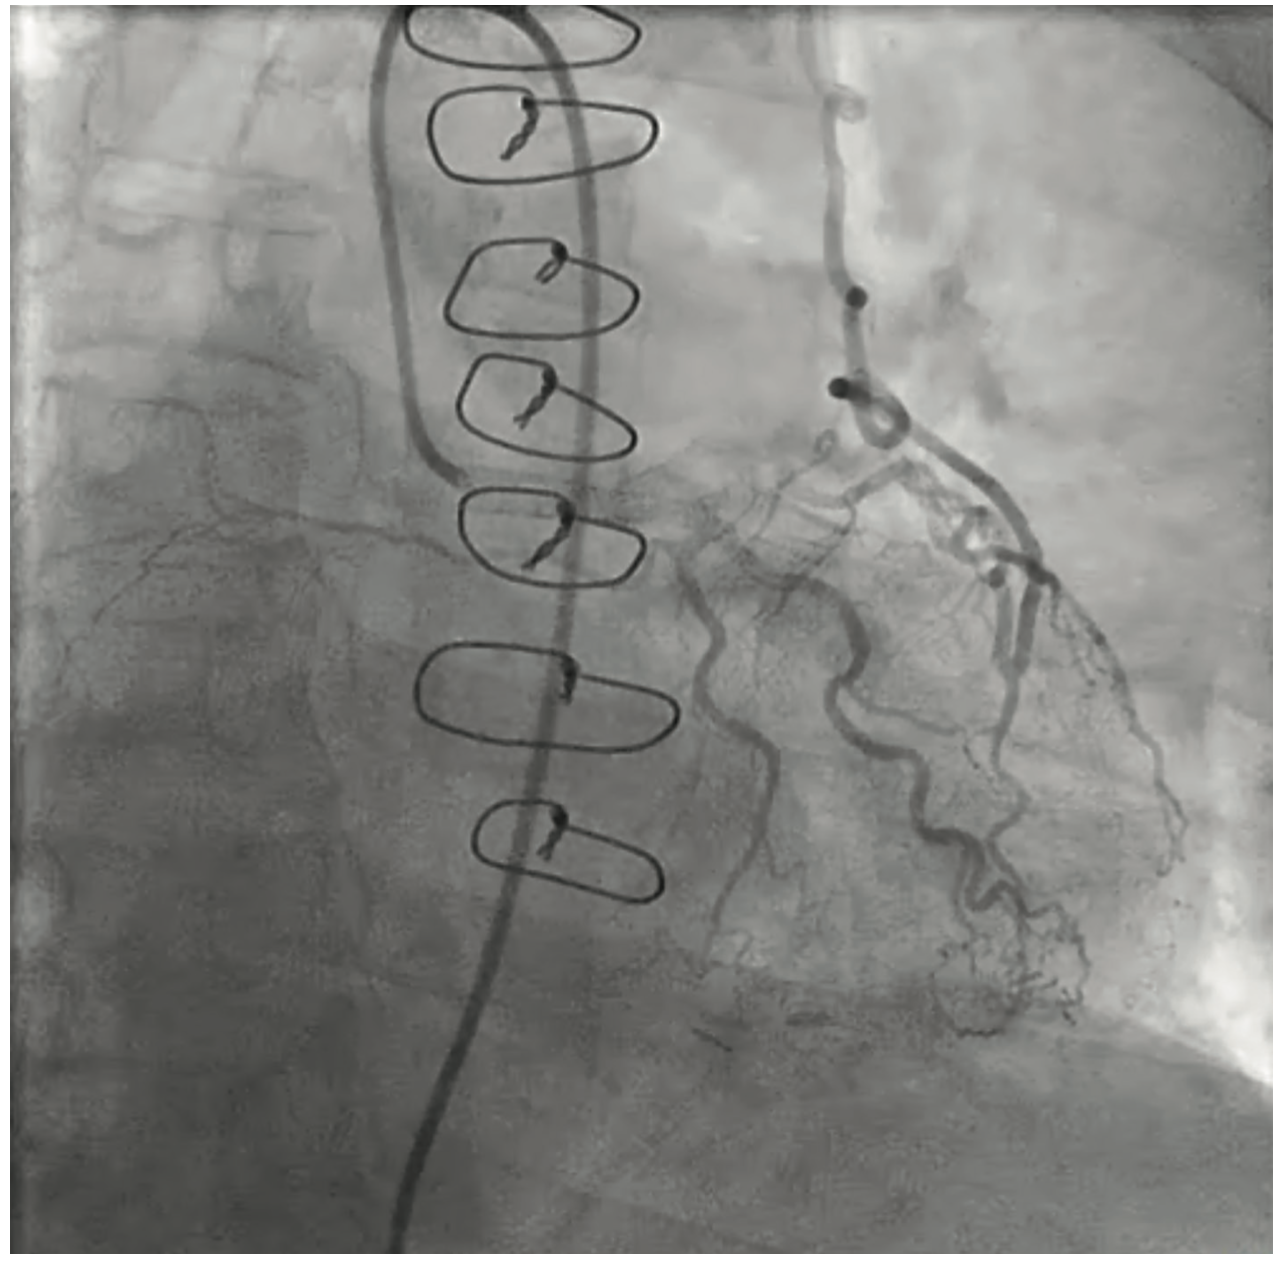

Figure 1. Retrograde blood flow from the left anterior descending coronary artery (LAD) into the left internal mammary artery (LIMA).

A 68-year-old gentleman presented to the emergency room with recurrent, substernal, exertional chest pain that was relieved with rest. His past medical history was significant for hypertension, diabetes, and coronary artery disease (CAD), for which he had undergone CABG with left internal mammary artery (LIMA) to left anterior descending artery (LAD) grafting and LAD stenting 12 years prior. He also had ischemic cardiomyopathy, bilateral renal artery stenosis, and peripheral arterial disease. Notably, on physical exam, there was discrepancy in blood pressure readings of his upper extremities, with 140/80 mmHg on the right, and 80/50 mmHg on the left. Electrocardiogram showed nonspecific ST-segment changes unchanged from prior and cardiac troponin was undetectable. Echocardiogram showed a mildly reduced ejection fraction of 45%, along with mild diastolic dysfunction and mild right ventricle systolic dysfunction. No new wall motion abnormality was seen. Given the blood pressure discrepancy, aortic dissection was considered and a computed tomography angiogram (CTA) of the chest, abdomen and pelvis was obtained. CTA ruled out dissection, but was suggestive of possible proximal left subclavian artery stenosis, a finding that raised the suspicion for CSSS as a cause of the patient’s recurrent angina. The patient underwent coronary and subclavian percutaneous angiography, which revealed patent LAD stents. There was 80% stenosis in the left subclavian artery proximal to the LIMA graft, with a 40 mmHg pressure gradient across the lesion. Retrograde and competitive flow was noted in both the distal LAD and vertebral arteries, confirming CSSS (Figure 1). Subsequent left subclavian lesion dilation and stenting was performed, resulting in brisk flow and resolution of patient’s symptoms (Figure 2).